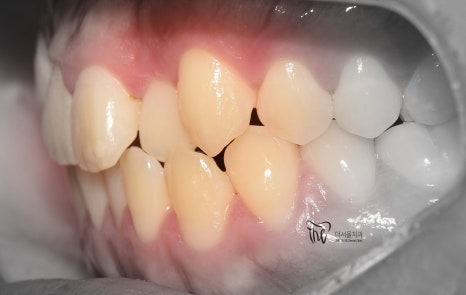

정면 및 측면에서 봤을 때, 측절치의 후방위치에

따라서 반대교합 형태를 보여주고 있으면서

이 때문에 송곳니가 더 덧니처럼 보여지는 느낌을

받고 있는 모습을 볼 수 있습니다.

나아가, 하악의 전치부 쪽에도 총생 현상이

같이 관찰이 되면서 이런 비심미적인 요소들을

개선시키고 싶은 마음으로 더서울치과에

내원하셨던 분입니다.